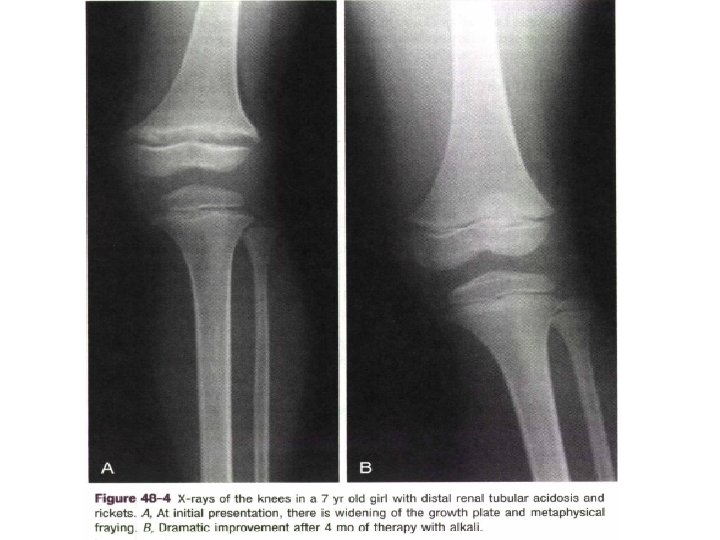

• In familial hypophosphatemic rickets, the major defect in mineral metabolism is failure of the kidney to reabsorb filtered phosphate adequately so that serum phosphate decreases, and urinary phosphate is high. • The diagnosis of this X-linked disease usually is made within the first few years of life. • Disease typically is more severe in males.

• Rickets usually is treated with 1, 25 hydroxyvitamin D and supplemental calcium. • In hypophosphatemic rickets, phosphate supplementation (not calcium) must accompany vitamin D therapy, which is given to suppress secondary hyperparathyroidism.

• Adequate therapy restores normal skeletal growth and produces resolution of the radiographic signs of rickets. • Nutritional rickets is treated with vitamin D in one large dose or multiple smaller replacement doses. • Surgery may be required to straighten legs in untreated patients with long-standing disease.